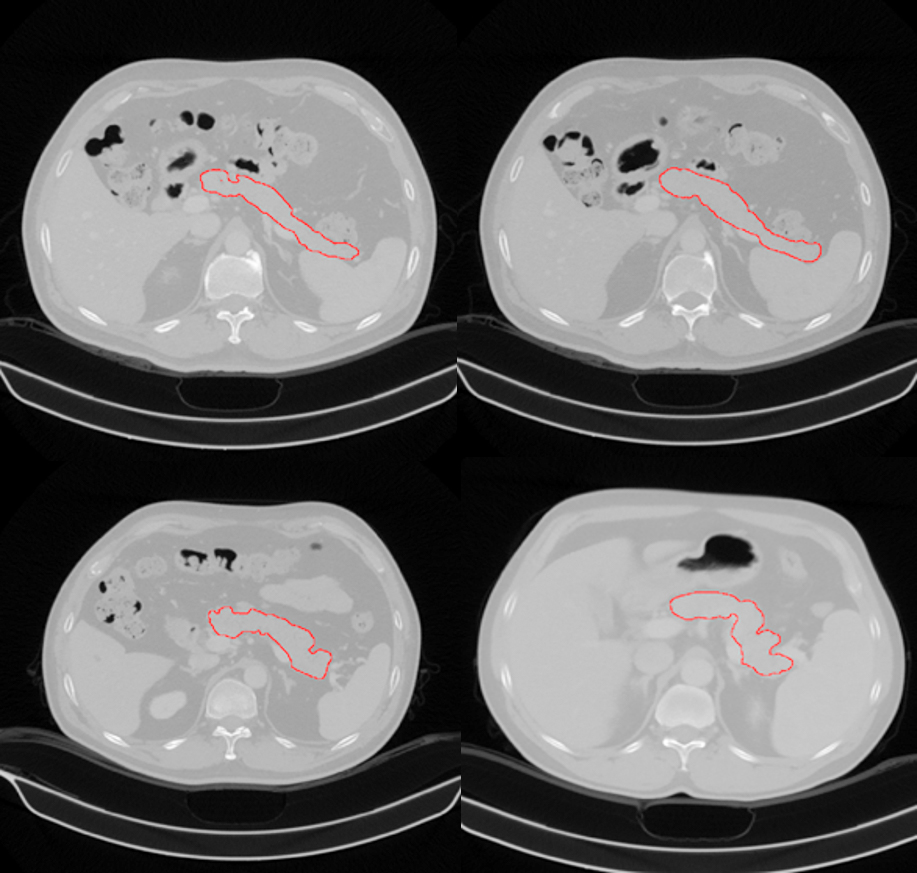

描红部分为王一达团队找出的胰腺位置

胰腺是人体最重要器官之一,具有内、外分泌功能。近年,胰腺疾病的发病率逐年上升,尤其是胰腺癌,为致死率最高的肿瘤之一,5年生存率小于1%。CT检查为诊断胰腺病变最主要的检查方式,随着数字医疗设备的进步和影像组学和深度学习等领域的发展,利用CT数据进行计算机辅助诊断,准确诊断胰腺病成为可能。而胰腺分割作为计算机辅助诊断基础而重要步骤,研究意义重大。由于胰腺的解剖结构较为复杂,其主要位于后腹膜,形态、位置变异较大,且周围有大量邻近组织,如胃、十二直肠、脾脏及大血管,这些组织在CT图像上与胰腺紧密相连且密度相似,再加上CT图像本身的噪声、局部体效应和组织运动的影响等因素,胰腺分割也是个具有很大挑战性的问题。